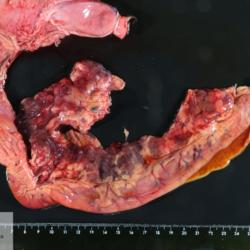

Avian (Poultry)

Liver

Lymphoma

Marek's disease